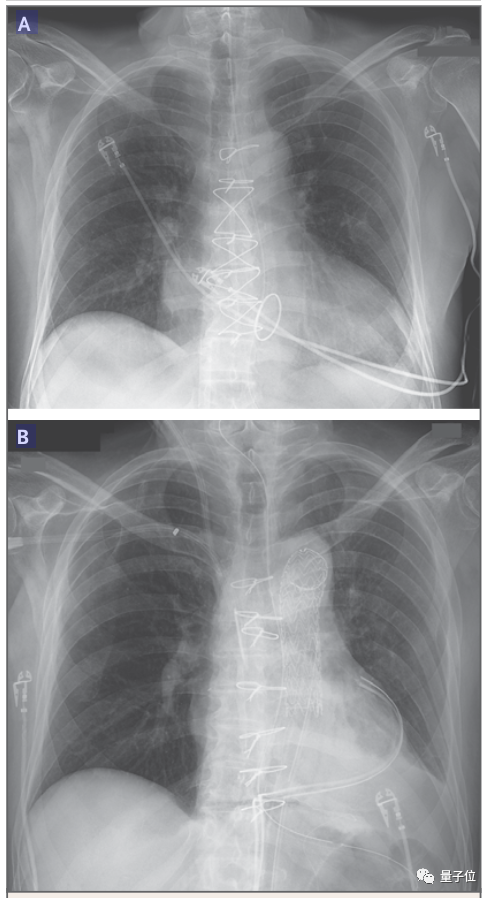

△图B中患者心脏增大

论文中表明,患者死后心脏重量几乎增加了一倍,从328克增长到600克。

心脏中出现了纤维化组织,伴有红细胞外渗现象。